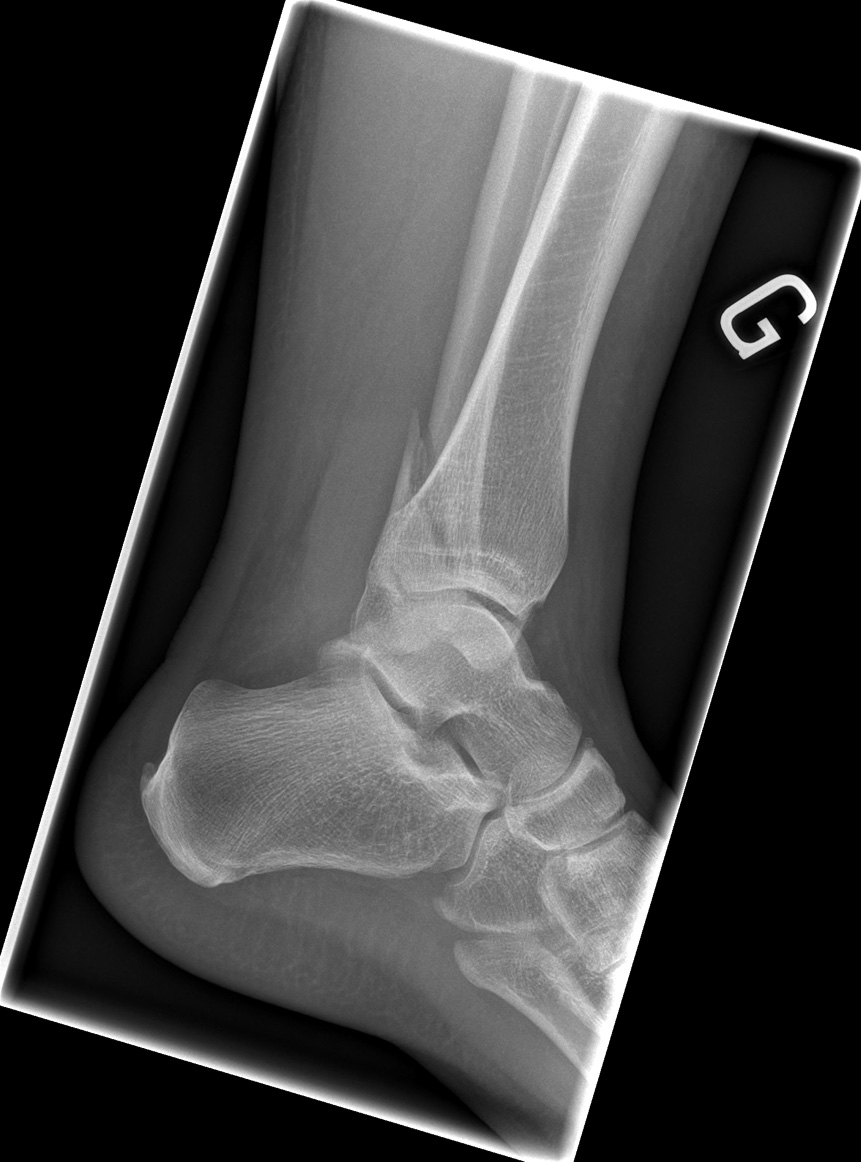

26-year-old male:

Ankle eversion trauma while playing soccer.

Bimalleolar fracture

Lateral malleolus oblique fracture (Weber B) concomitant to a medial malleolus transverse fracture.

Intact posterior malleolus

The posterior malleolus appears intact.

Lateral